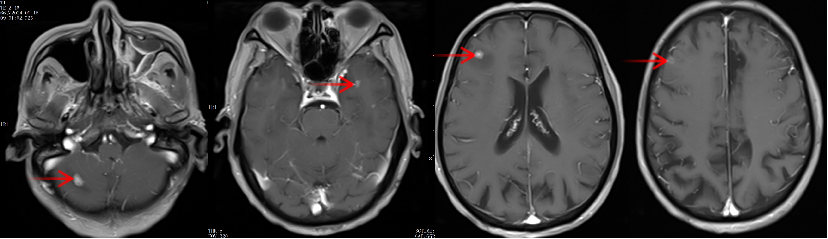

林老先生,67歲,患者2024年8月因咳嗽、咳痰,并發(fā)現(xiàn)頸部包塊入院。入院后經(jīng)CT檢查發(fā)現(xiàn),肺內(nèi)及頸部可見多發(fā)腫瘤病灶(見圖)。于2024年8月21日行超聲引導(dǎo)下頸部淋巴結(jié)穿刺活檢術(shù)。術(shù)后病理提示:右頸轉(zhuǎn)移性肺腺癌。頭部磁共振檢查顯示,顱內(nèi)多發(fā)腦轉(zhuǎn)移瘤病灶(見圖)。診斷為肺腺癌,腦、頸部淋巴結(jié)、肺內(nèi)多發(fā)轉(zhuǎn)移IVB期。進(jìn)一步對(duì)患者腫瘤組織進(jìn)行腫瘤組織基因檢測(cè)和免疫檢查點(diǎn)分子——細(xì)胞程序性死亡配體1(PDL1)檢測(cè)。

圖注:磁共振檢查,顱內(nèi)多發(fā)腦轉(zhuǎn)移瘤病灶。

患者基因檢測(cè)結(jié)果為陰性,沒有找到具有靶向治療藥物的突變基因。此外,患者年齡較大,體質(zhì)非常瘦弱,全身多發(fā)轉(zhuǎn)移病灶,為治療帶來了巨大的挑戰(zhàn)。然而,患者PDL1檢測(cè)顯示,PDL1高表達(dá)(PD-L1患者TPS98% CPS100%),提示免疫治療有效率較高。潘振宇教授團(tuán)隊(duì)為患者制定了個(gè)體化精準(zhǔn)腫瘤治療方案,患者于2024年9月21日開始接受頭部放療。采用最新一代智慧化精準(zhǔn)放療系統(tǒng)——Halcyon“速銳刀”,成功控制患者全部顱內(nèi)病灶。治療過程順利,沒有副反應(yīng)發(fā)生。隨后,給予患者每3周1次免疫治療。經(jīng)過3次免疫治療后復(fù)查,患者肺內(nèi)病灶顯著縮退,癥狀明顯恢復(fù),沒有明顯副反應(yīng)發(fā)生。目前狀態(tài)恢復(fù)良好,生活完全自理。

圖注:治療后復(fù)查磁共振顯示,T1增強(qiáng)掃描可見顱內(nèi)強(qiáng)化轉(zhuǎn)移病灶較前明顯縮退,部分消失。